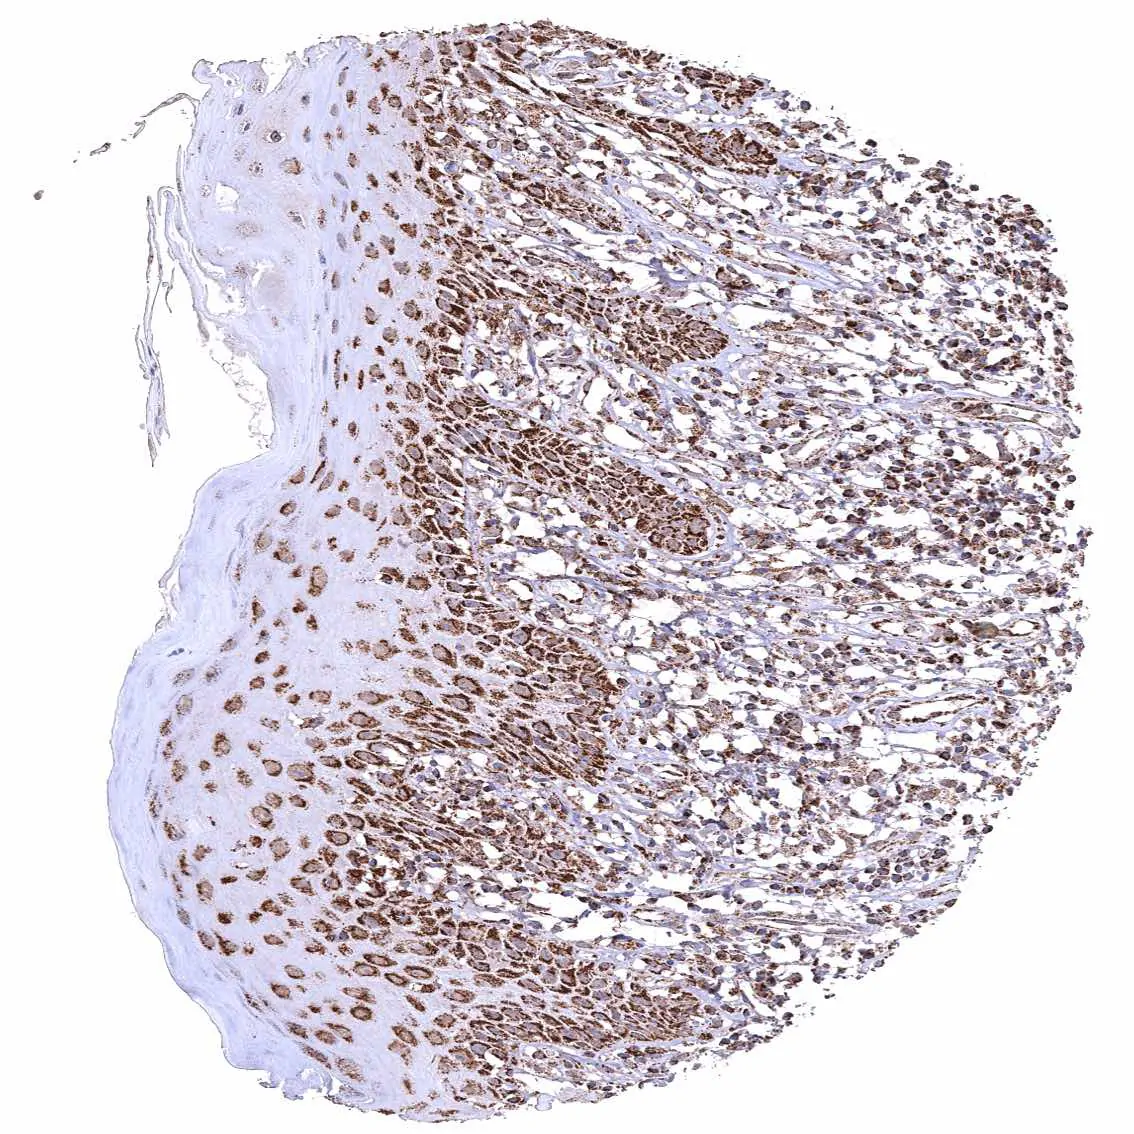

Uterus, ectocervix – Distinct granular, perinuclear, cytoplasmic ATP5J staining in all cell types. The staining is least intense in superficial cell layers of non-keratinizing squamous epithelium.